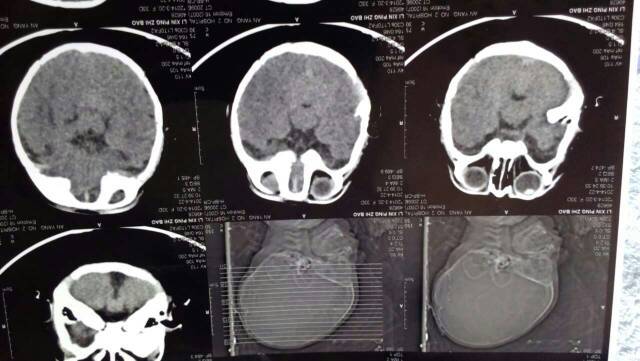

我儿子满月时候的ct,说是轻度脑发育不全,打了5天营养针,还需要继续打吗?

婴幼儿脑部发育不良一般做脑细胞活化的治疗,一个疗程是10-14天的,建议几次做治疗5天左右比较好的。

早期脑发育不好,需要足疗程护脑药物干预的,每疗程需要10天左右,最好是坚持三疗程的。配合早期被动操,水疗等干预最好。